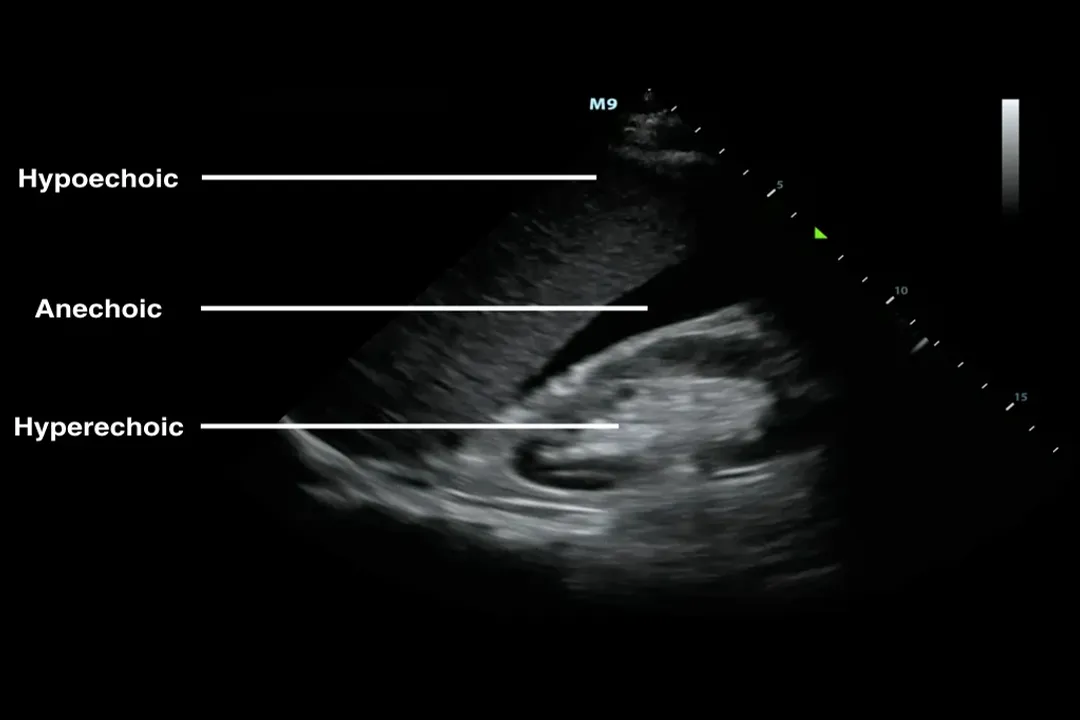

# B-Mode Imaging

The most common format is B-mode, which stands for brightness mode. [6][8] In this mode, the brightness of each dot on the screen corresponds to the intensity of the received echo. [6] A very bright dot indicates a strong reflection (like a solid structure or bone), while a dark or black area indicates that sound passed through unimpeded (like a simple fluid-filled structure, such as a bladder or a simple cyst). [7] B-mode creates the familiar, cross-sectional gray-scale images seen in many diagnostic reports. [6]